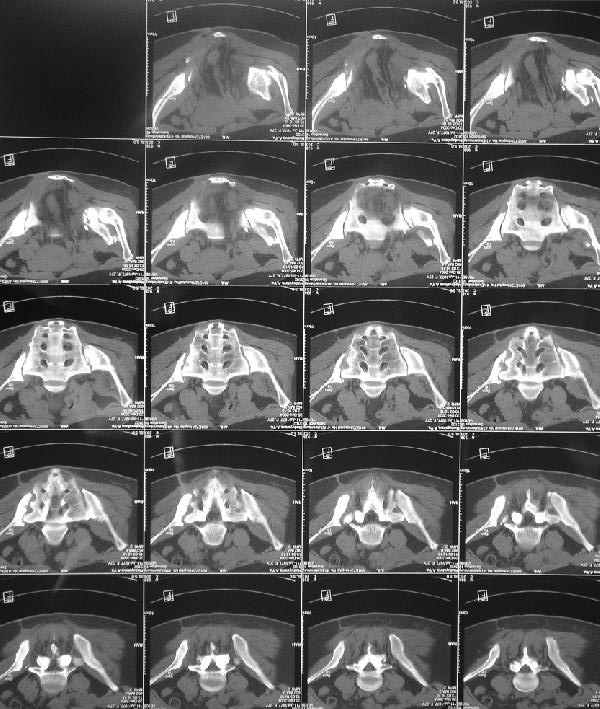

Should you deem her fit for surgery, the 3-D CT alone is insufficient for planning preoperatively. We can¹t see the healing response, soft tissue envelope, the right SI injury, nor the left SI joint problem well enough on the 3-D CT alone.

По просьбам коллег отправляем снимки таза: прямая, inlet, outlet, 2 дополнительные компьютерные томограммы.

О виртуозности владения аппаратным лечением, неоднократно доказанным на ваших материалах, со стороны русских коллег, все таки голосую за многоэтапность лечения, конечно после нормального обследования, снимки таза: прямой, инлет, оутлет и КТ, а представленная 3D, не представляю

во сколько обошлась больной, кроме красивого рисунка, не дает нужную информацию для специалиста. Обычные КТ срезы дают информацию о

сращении, от которого и зависит тактика лечения.